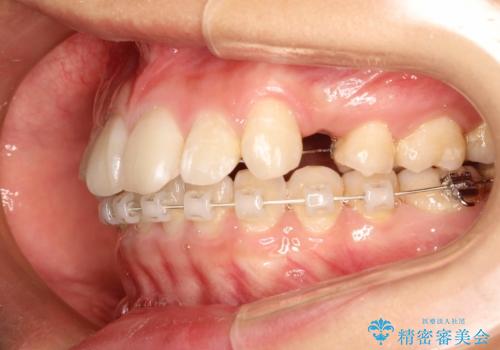

ハーフリンガル矯正 抜歯をして前歯を下げる

- ハーフリンガル

- 1年8ヶ月

- 上顎の両側第1小臼歯抜歯による抜歯矯正を計画した。

上顎の抜歯により上の前歯の位置を大幅に後ろに下げることができます。